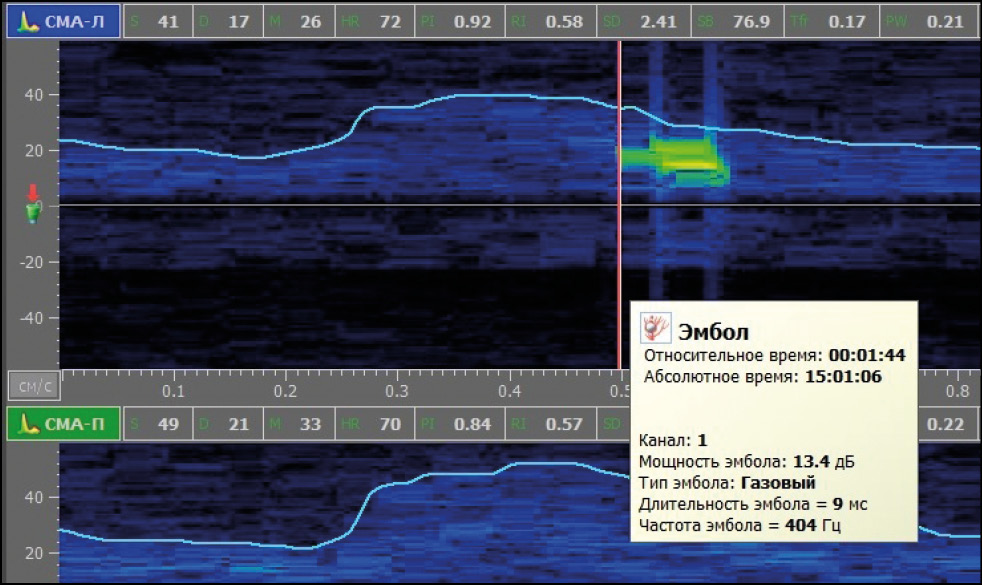

В случае наличия признаков микроэмболии в режиме постобработки мониторинга оценивали интенсивность (количество МЭС в час), для каждого МЭС длительность (мс) — косвенную характеристику размера эмбола, частоту (Гц) — косвенную характеристику структуры эмбола, мощность (дБ) — интегральную характеристику микроэмбола [3]. Пример оценки характеристик МЭС представлен на рис. 1, 2.

Рис. 2. Оценка биофизических характеристик микроэмболических сигналов при постобработке ТКДМ с МЭД